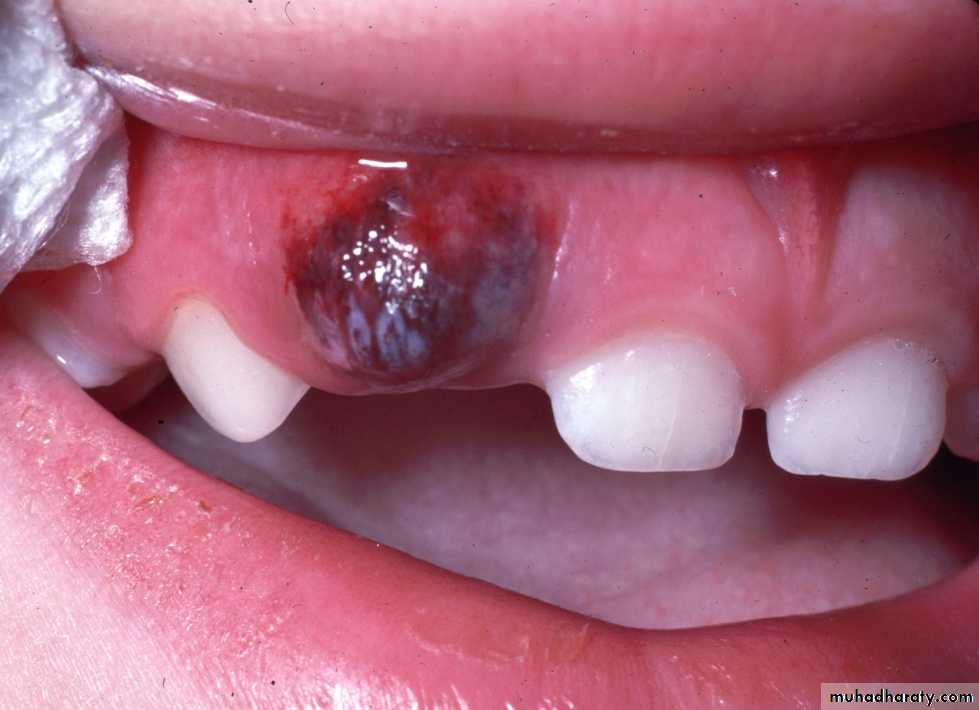

Eruption Haematoma (Eruption Cyst):

Bluish purple elevated areaResult from trauma to the area and a hemorrhage on follicle of erupted tooth.

subside after eruption

Mainly associated with 6s

and Es.

Treatment: Self limited

as the tooth break through

or surgical excision.